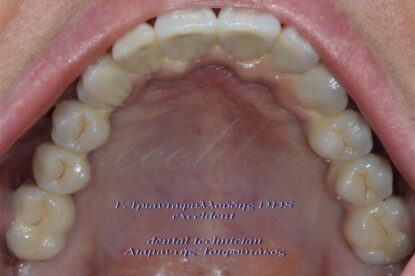

Ακόμη ένα περιστατικό ολικής στοματικής αποκατάστασης ασθενούς με ακίνητες γέφυρες στηριζόμενες σε εμφυτεύματα(8 στην άνω και 7 στην κάτω γνάθο).

Η συγκεκριμένη ασθενής είχε κατά το παρελθόν κατασκευάσει πλήθος οδοντοστοιχιών(μασέλες), τις οποίες απέρριπτε καθώς είχαν ελλιπή συγκράτηση και της δημιουργούσαν αντανακλαστικό εμέτου.

Με τις νέες ακίνητες αποκαταστάσεις επανήλθε τόσο η αυτοπεποίθηση και η άνεση της ασθενούς όσο και η μασητική της ικανότητα στα προ της απώλειας των δοντιών της επίπεδα.